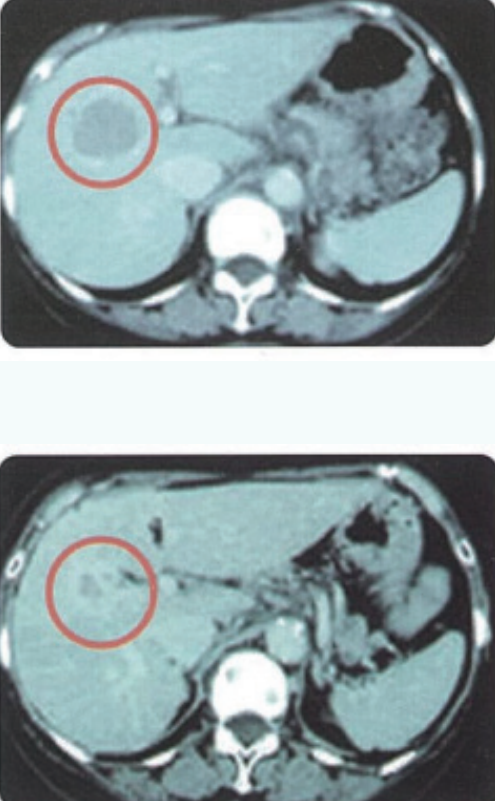

战果展示:晚期肝癌患者病情得到有效控制

一位70多岁的女性患者,有25年的丙肝和肝硬化病史。身体不适后经CT检查,发现肝脏右叶有一个4.5cm的大肿瘤,并伴有多个小肿瘤,被诊断为无法手术的多发性肝细胞癌。随后,患者接受了以“复合细胞治疗”为核心的方案。疗效评估显示:肿瘤标志物(AFP及PIVKA-II)显著下降,影像学证实肿瘤缩小、其余病灶稳定,且未出现腹水,病情得到有效控制。